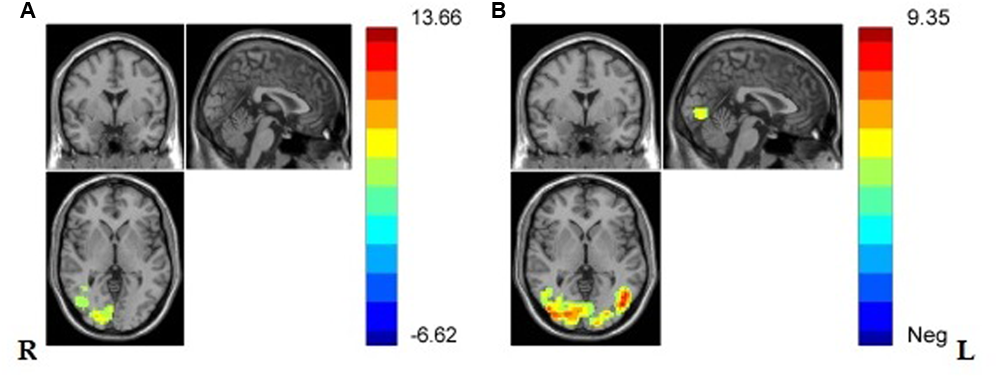

And one sample t-test in VG and NG was separately conducted and the results showed that, in both groups, regions in lateral occipital gyrus, lateral fusiform gyrus, right middle temporal gyrus, and the Secondary visual cortex (V2) were significantly activated (see Figures 4A,B and Table 2).

FIGURE 4

(A) Brain regions showing significant activation while viewing painful stimuli compared with non-painful stimuli in NG in lateral middle occipital gyrus, lateral V2, right middle temporal gyrus, lateral fusiform gyrus. (p < 0.001, Alphasim corrected; k > 1138). (B) Brain regions showing significant activation while viewing painful stimuli compared with non-painful stimuli in VG in lateral occipital gyrus, lateral fusiform gyrus, left V2, and right middle temporal gyrus (p < 0.001, Alphasim corrected; k > 1132).

Brain regions showing significant activation in lateral occipital gyrus, lateral fusiform gyrus, left V2, and right middle temporal gyrus in VG, and significant activation in lateral occipital gyrus, lateral fusiform gyrus, right lingual gyrus, left V2, and right middle temporal gyrus while viewing painful stimuli compared with non-painful stimuli (p < 0.001, Alphasim corrected; k > 1132 in VG and k > 1138 in NG).